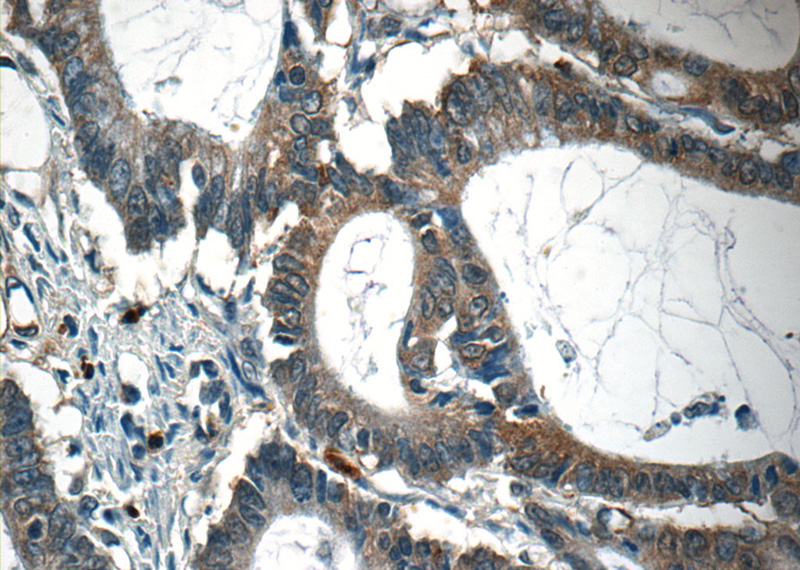

Immunohistochemistry of paraffin-embedded human colon cancer tissue slide using Catalog No:108844(CAPZA1 Antibody) at dilution of 1:50 (under 40x lens)